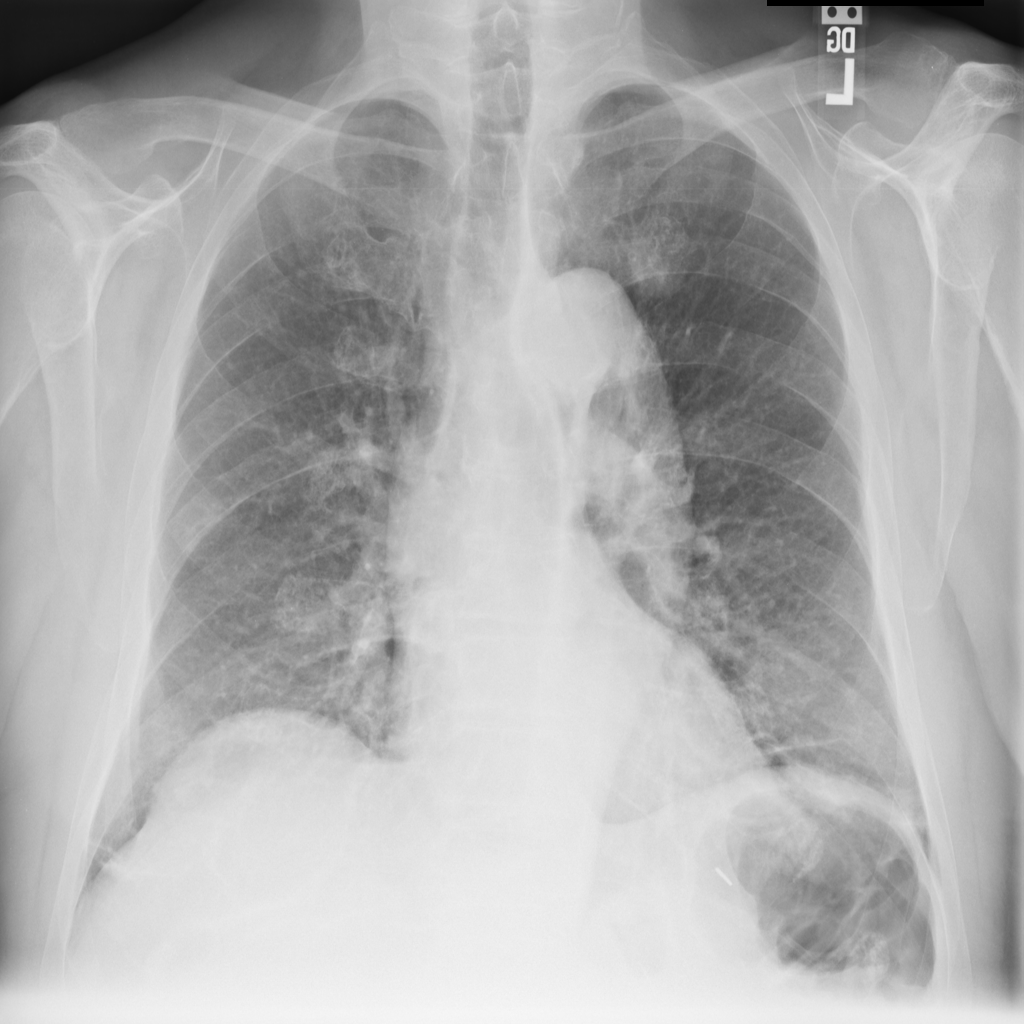

Showing up to 90 reference images for Emphysema.

PAT-0E82 · IMG-000Emphysema

PAT-0E82 · IMG-000

AP